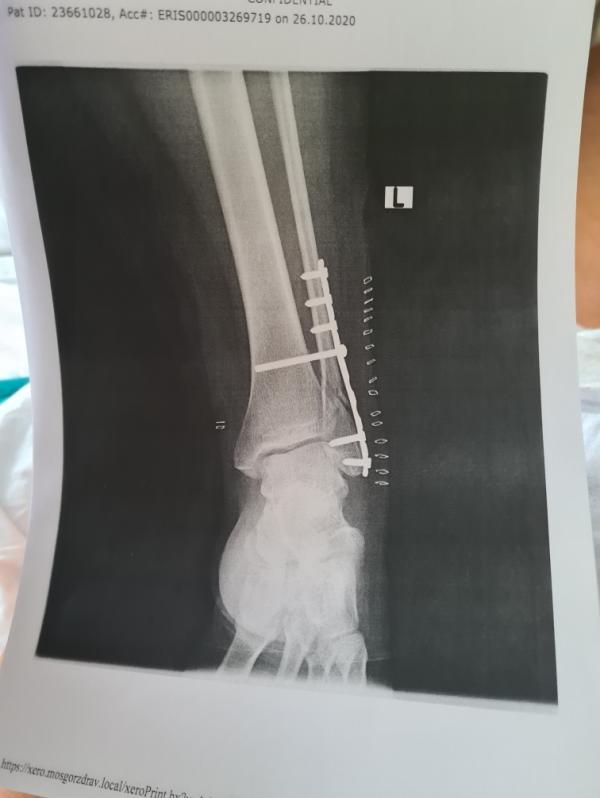

Терминатор дома. Через 6 недель следующая операция. После этого буду потихоньку вставать на сломанную ногу. Берегите себя!

Мне через 6 недель самый длинный винт вынимать. А остальные и пластину через год-полтора